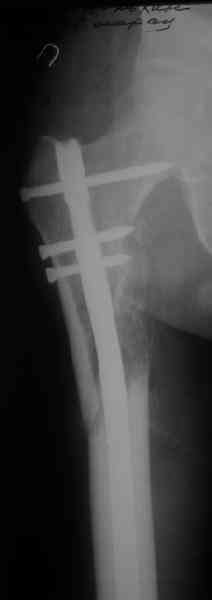

Вот несколько. С тисками и трубой на днях сделаем.

"Судя по уровню перелома, винты в шейку избыточны, подойдет и диафизарный гвоздь. Все, что нужно, это тиски и труба. Загнуть сразу ниже отверстий градусов на 8-10, и вся недолга. Последние годы у нас это рутинная практика. Предызогнутые еще с завода гвозди неудобны тем, что они уже правый-левый."

Конечно. Чтобы не сломать, лучше проложить в тиски сразу ниже отверстий полоску металла, чтобы там создалась концентрация напряжений при изгибе, а не на уровне отверстия.

Гвозди с латерализованным проксимальным концом сейчас становится мэйнстримом, поскольку трохантерная точка входа во всех отношениях

благоприятнее f. piriformis.